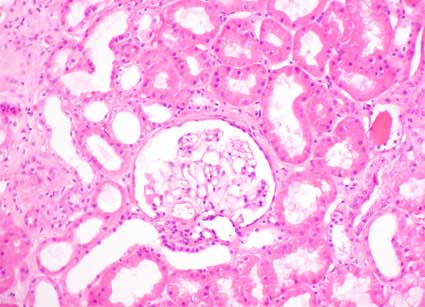

Figura 1.

H&E, X200.